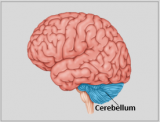

La neuroanatomie est la branche de l'anatomie qui étudie l'anatomie du système nerveux, c'est-à-dire la structure, la fonction et l'organisation du système nerveux.

Le système nerveux est l'un des systèmes les plus complexes du corps humain, et il comprend le cerveau, la moelle épinière, les nerfs périphériques et les ganglions nerveux. La neuroanatomie s'intéresse à la manière dont ces structures sont reliées les unes aux autres, comment les signaux sont transmis entre les cellules nerveuses, et comment les différentes parties du système nerveux travaillent ensemble pour contrôler les fonctions corporelles et cognitives. Les neuroanatomistes utilisent des techniques d'imagerie avancées, comme l'imagerie par résonance magnétique (IRM), la tomographie par émission de positons (TEP) et la microscopie pour visualiser les structures et les fonctions du système nerveux.